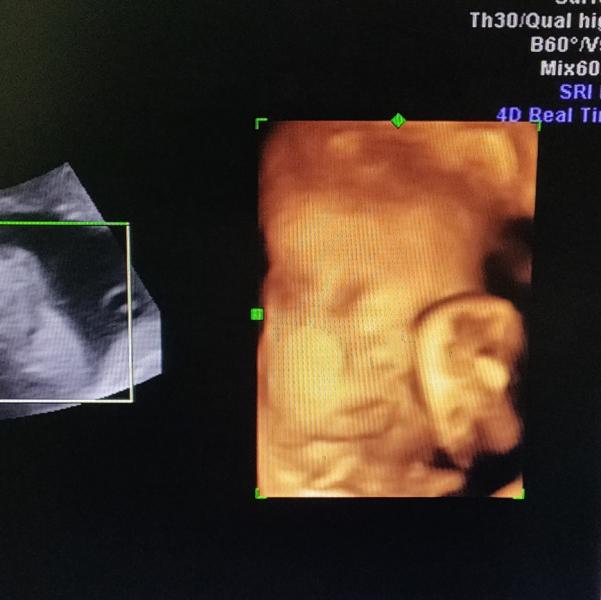

Были сейчас на еще одном УЗИ в Бендерах, очень понравился врач, и по цене в два раза меньше, чем у других узистов ( а была я на скринингах , наверное, у половины врачей по Приднестровью). Пожалела, что не узнала о нем раньше.

Так еще он единственный, кто сделал 4Д снимок, хотя срок уже довольно большой , чтобы личико хорошо было видно. Малыш постоянно отворачивался и закрывался ручками.

Несмотря на это, удалось поймать кусочек лица, я там чуть не разрыдалась от умиления , когда увидела))) Мног...